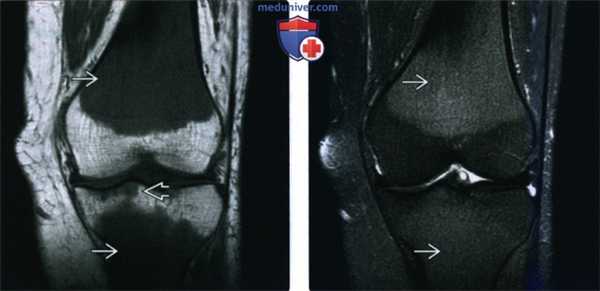

(Слева) МРТ Т2 ВИ аксиальная проекция, с подавлением сигнала от жира: гиперинтенсивный костный мозг. Кортекс выглядит неизмененным; крошечные каналы, проходящие через кортикальный слой, позволяют кольцевидному мягкотканному компоненту развиваться. Компонент может быть небольшим, как в этом случае, либо достигать крупных размеров. Этот пациент ВИЧ-инфицирован, что может служить предрасполагающим к развитию лимфомы фактором.

(Справа) МРТ, сагиттальная проекция, режим Т1: низкоинтенсивный костномозговой сигнал от проксимального отдела плечевой кости. Визуализируется небольшой передний мягкотканный компонент, распространяющийся через кажущийся неизмененным кортикальный слой. (Слева) МРТ Т2ВИ, аксиальная проекция, с подавлением сигнала от жира: у этого же пациента визуализируется неоднородный высокоинтенсивный сигнал от костного мозга. Также наблюдаются многочисленные зоны фокального распространения опухоли через кортикальный слой, формирующие мягкотканный компонент. Признаки нарушения целостности кортикального минимальны.

(Слева) МРТ, корональная проекция, режим T1: патологический сигнал от костного мозга вокруг коленного сустава и очаговое поражение остаточных эпифизов.

(Справа) МРТ, корональная проекция, режим Т2, с подавлением сигнала от жира: патологический сигнал от костного мозга характеризуется лишь умеренной гиперинтенсивностью, что характерно для красного костного мозга. Тем не менее, вовлечение остаточных эпифизов служит явным признаком возможности диффузной инфильтрации костного мозга и должно указывать на необходимость дополнительною обследования. Пункция костного мозга позволила выявить острую лейкемию.